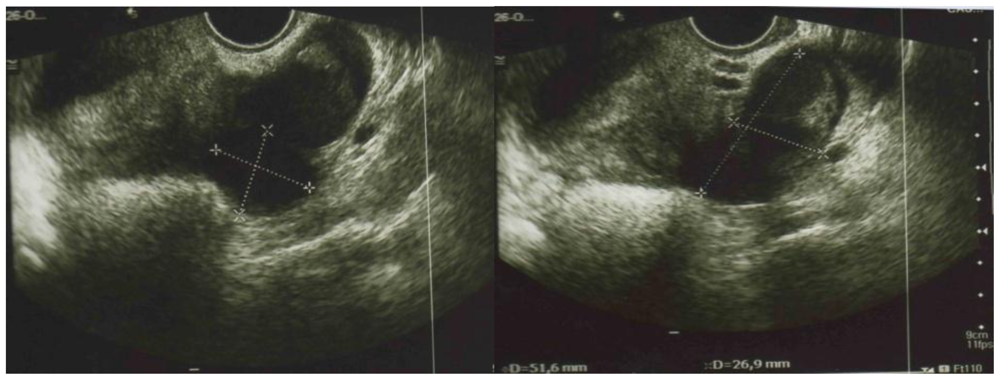

2. Case Presentation and Discussion